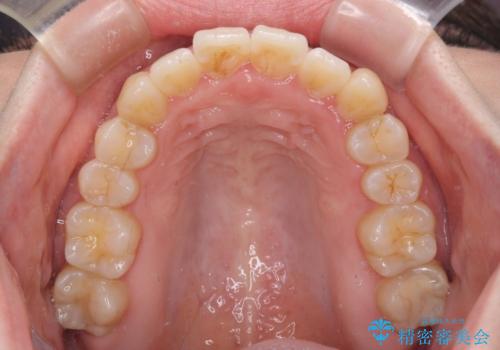

口元の突出感を改善 インビザラインによる非抜歯矯正

- 前歯がデコボコした上に口元が閉じにくいことを気にして来院された患者様です。

IPR(歯と歯の間を削る)と側方拡大では口の閉じにくさは改善できそうになく、一方で抜歯矯正を行うほどの突出感は認められませんでした。

親知らずを全て抜去し、歯列全体を後方に移動させることで口元の閉じにくさいを改善していくこととしました。

インビザラインでの歯列全体の後方移動は時間がかかりますが、しっかりと装着時間を守っていただいたので、スッキリとした口元に仕上げることができました。